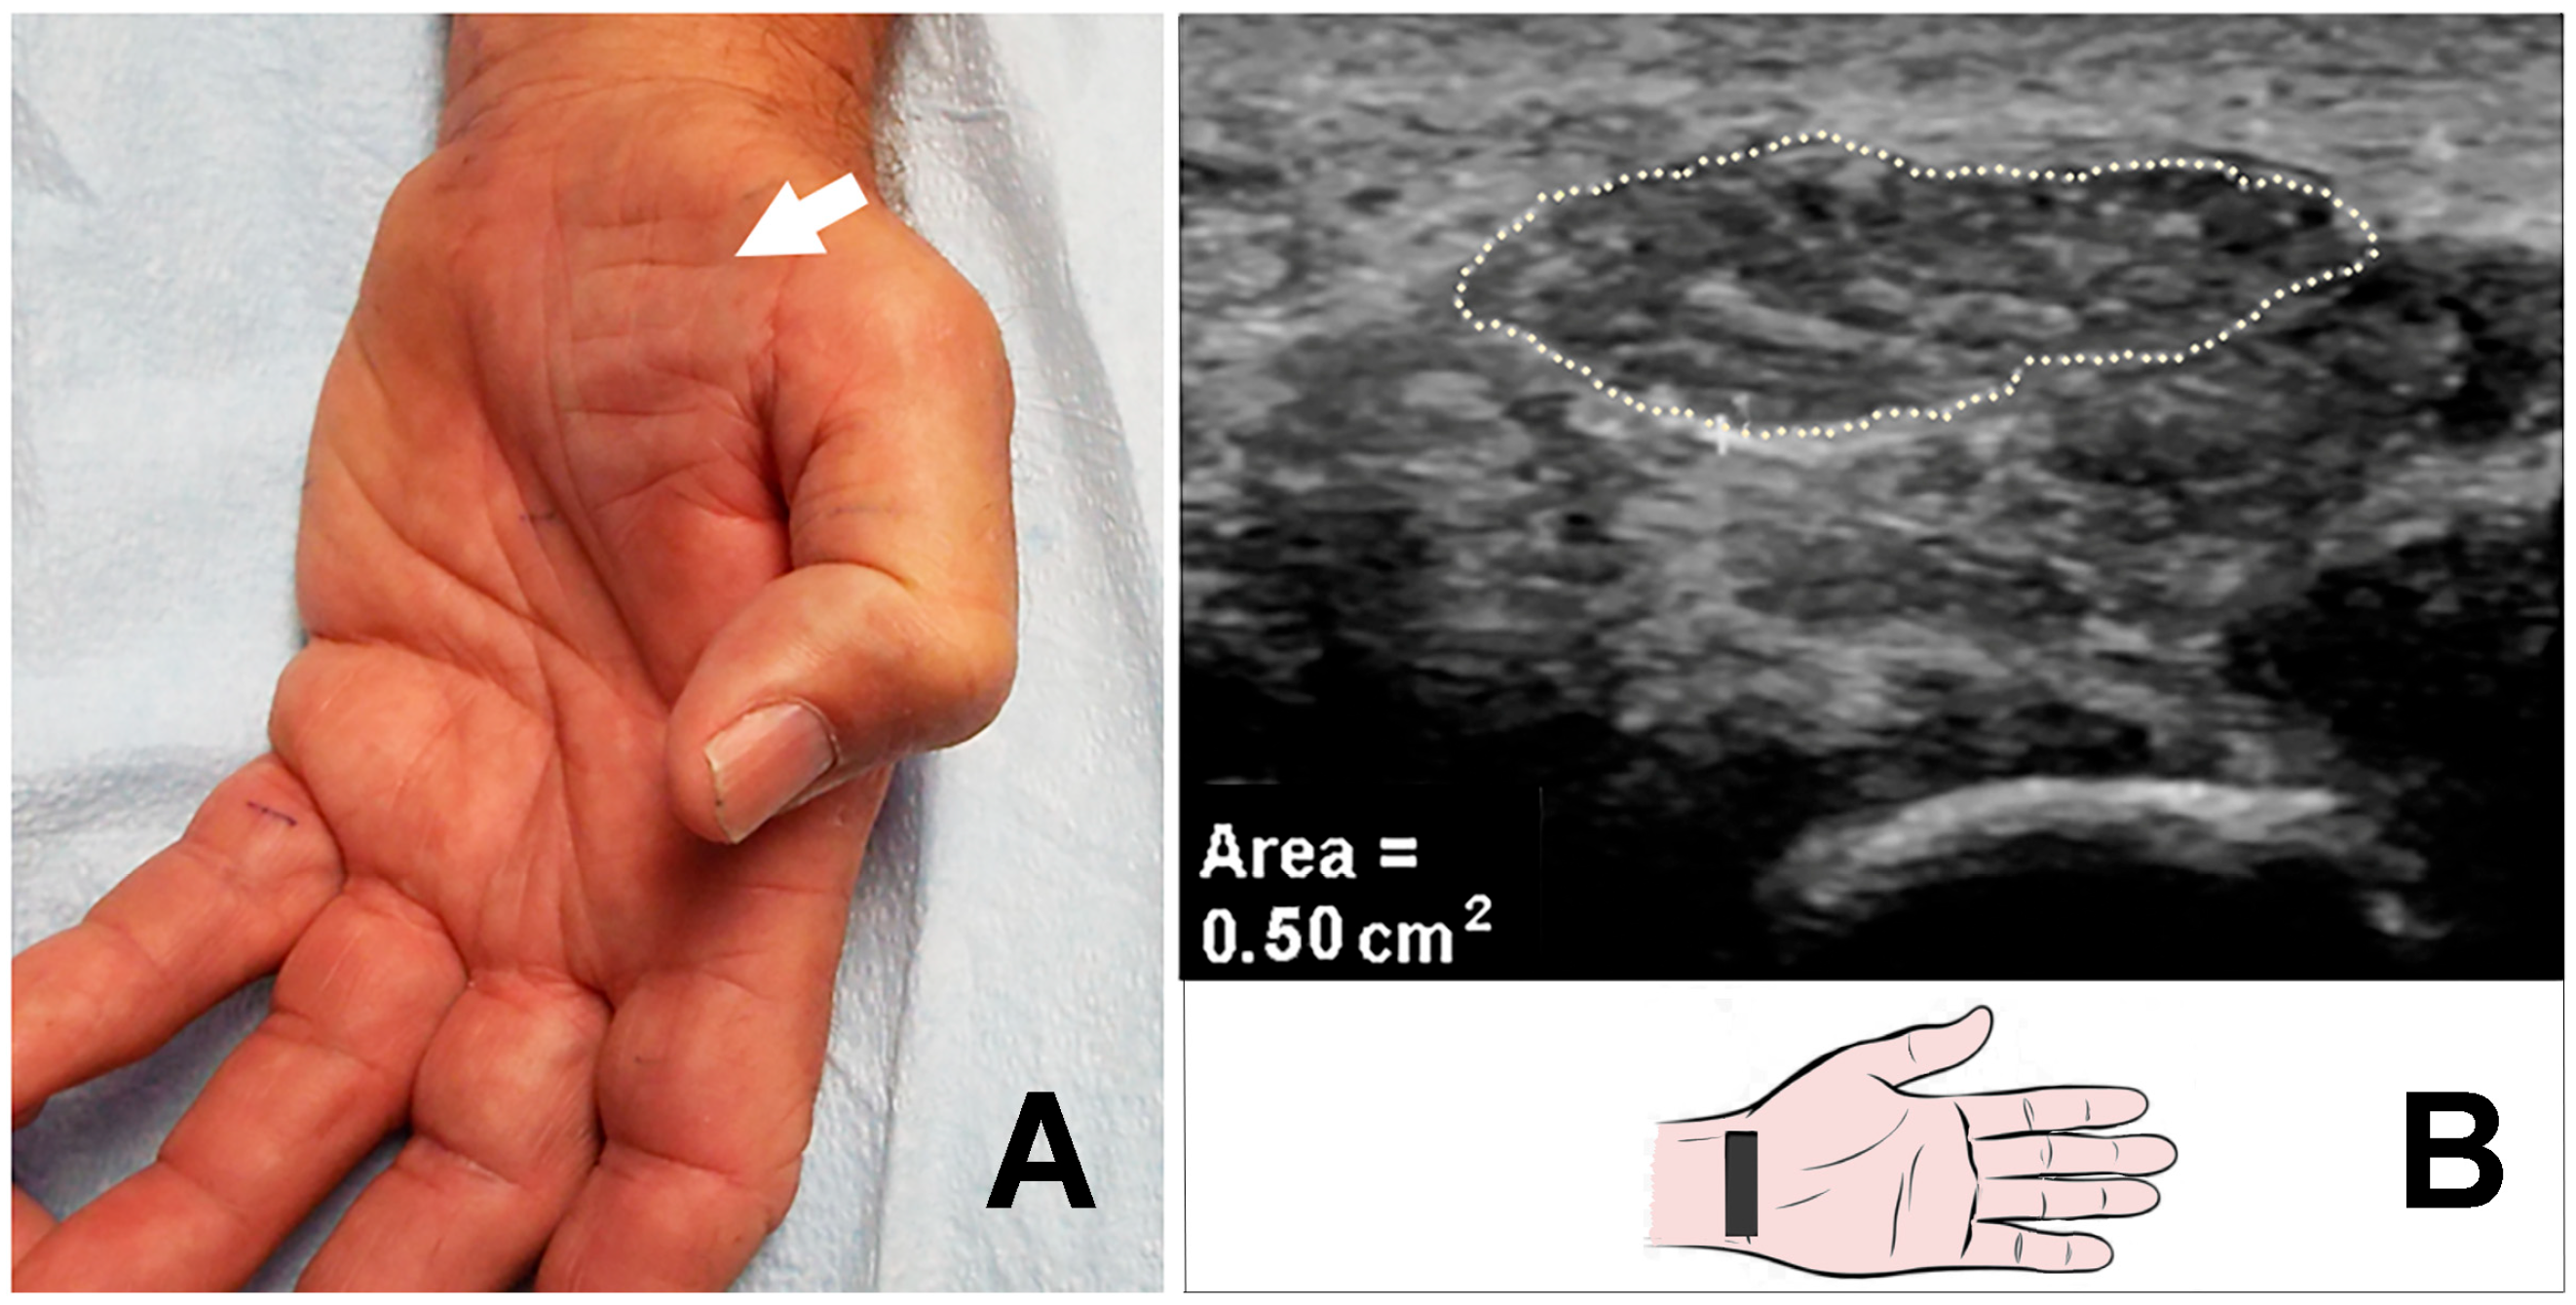

The markedly enlarged median nerve was detected by US in a total of 39 hands (36 patients, with 3 bilateral) (Table 2). Of the 39 hands, thenar atrophy was observed in 15 (38.5%) hands, and pinprick loss was noted in all 39 (100%) hands (Figure 1A–D, Figure 2A,B). Of the 39 hands, 3 (7.7%) hands had previously undergone a carpal tunnel release (CTR) procedure.

Figure 2. (A) Severe thenar muscle atrophy. (B) Massively increased CSA (50 mm2) of the median nerve (arrow) at carpal tunnel inlet. CSA: cross-sectional area.